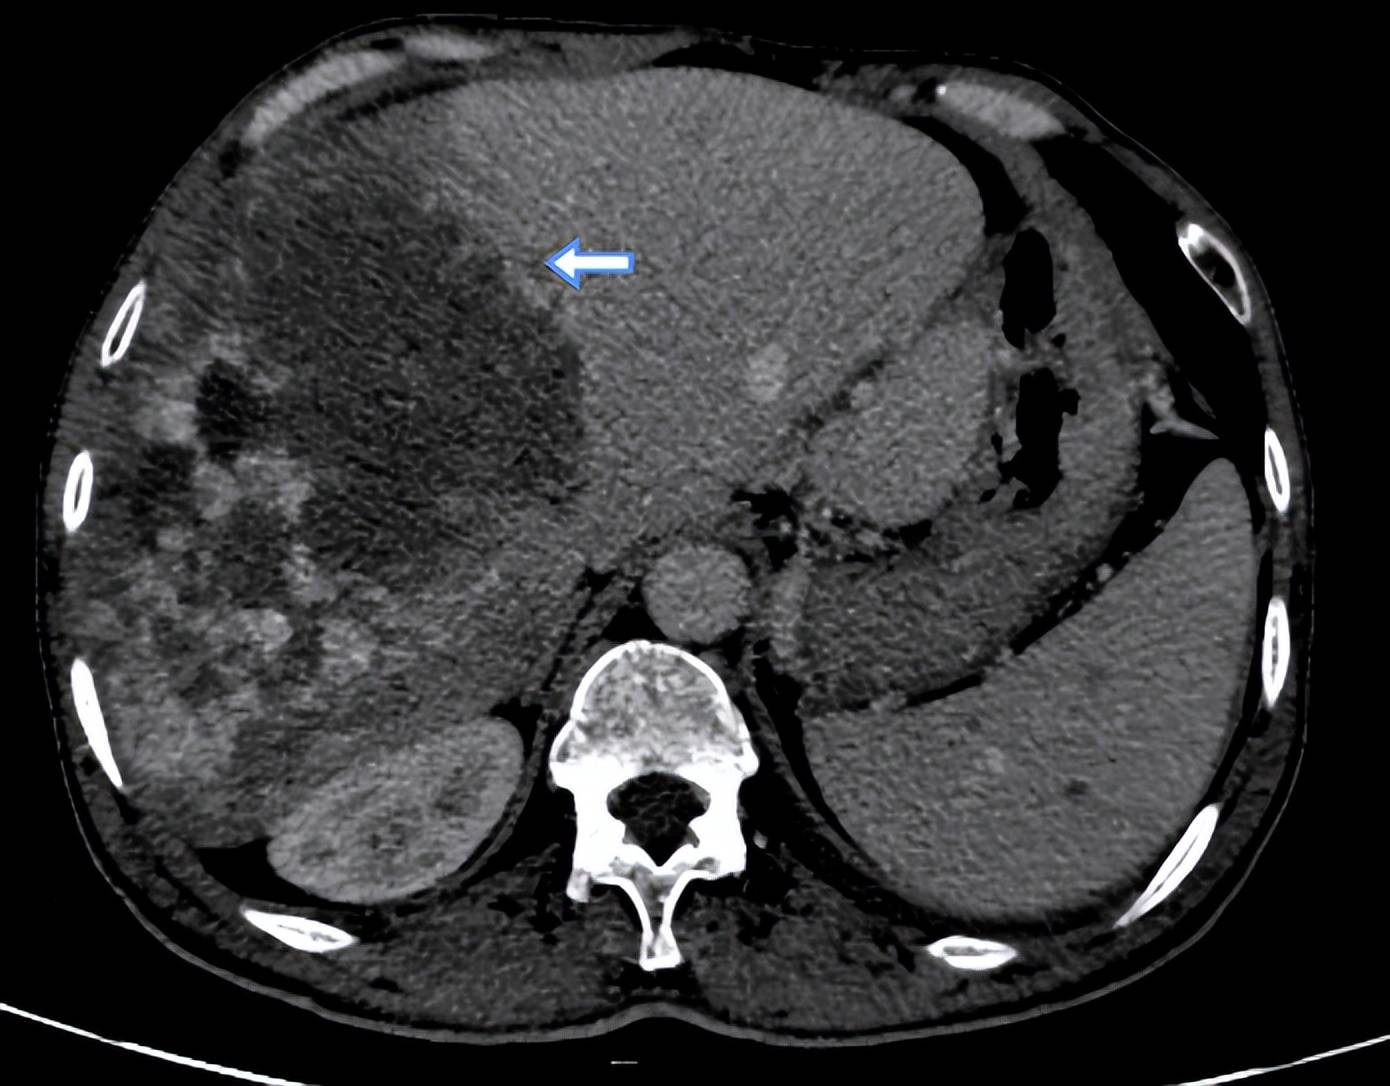

肝海绵状血管瘤的影像诊断

目前,影像学检查(如b超,ct,mri)是诊断肝血管瘤的主要方法

读书笔记-肝脏良性肿瘤的影像学特征

一图学习肝囊肿,血管瘤,转移瘤,fnh,肝腺瘤,肝癌的mr影像表现

肝脏上皮样血管内皮瘤影像表现